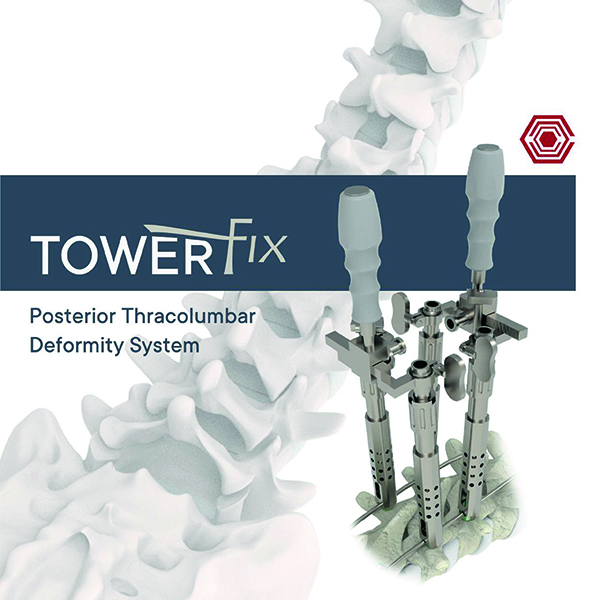

Towerfix

Akif Kaya Aybek

Norm Akademi

- Surgical Technique

- Intrument Container

- Instrument Types

Cerrahi Teknikler Eğitimi

- Towerfix Cerrahi Teknikler